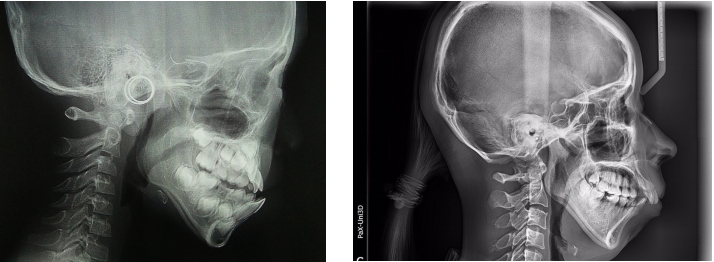

影响骨性下巴后缩矫治效果的主要因素是下颌骨垂直向发育的趋势,也就是高角、低角或者均角。

均角或者低角的骨性II类早期矫治效果通常会好。毕竟下颌骨的发育是正常的,随着生长的进行,下颌会逐步向前向上逆时针生长和改建,这是矫治骨性II类最需要的治疗方向。

而高角下巴后缩矫治效果相对均角或者低角下巴后缩,矫治效果需要的时间和下的功夫更多。